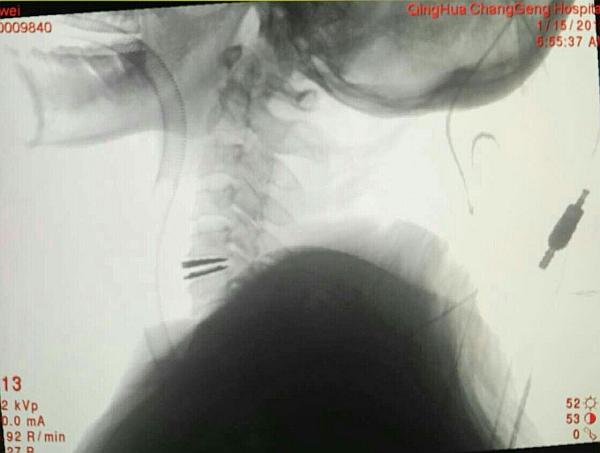

术中O-ARM确定人工椎间盘位置好

手术顺利,手术时间2小时,出血30毫升,术后患者双上肢麻木好转。